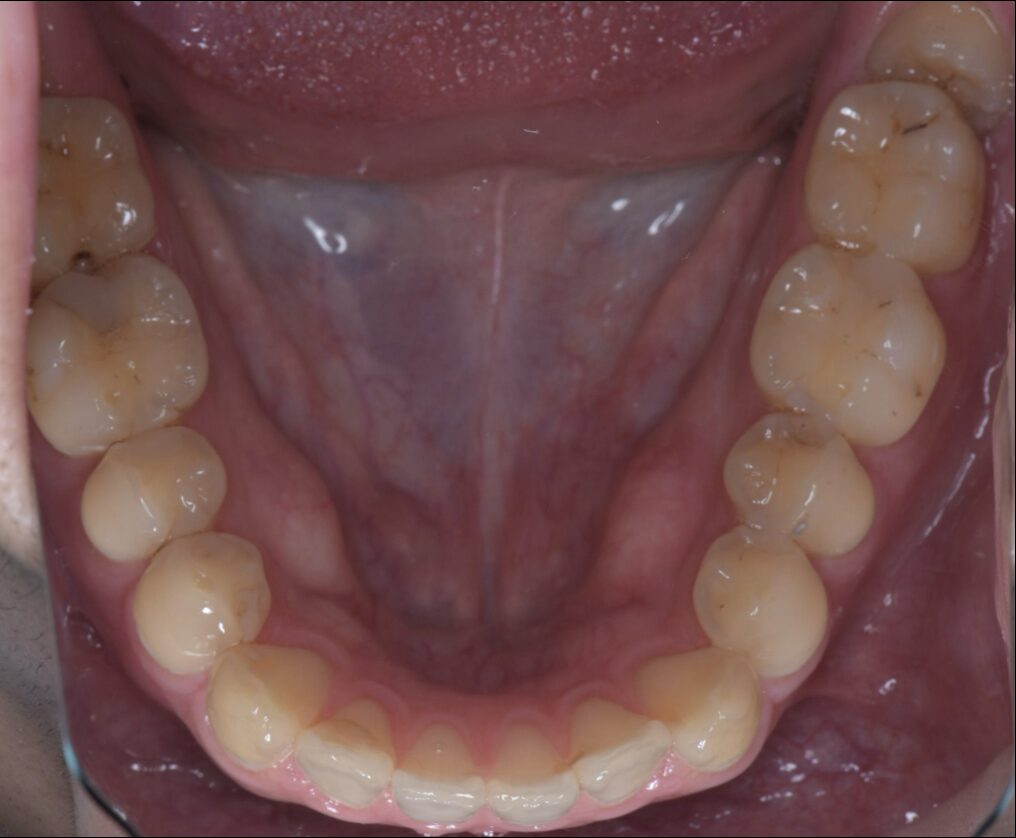

セラミック / 審美歯科

セラミックインレーにて治療した症例

Before

| 治療内容 | セラミックインレー(2本) |

| 治療期間・治療回数 | 2回 |

| 治療費用 | 143000円(税込) |

| 備考 | 40代 女性 |